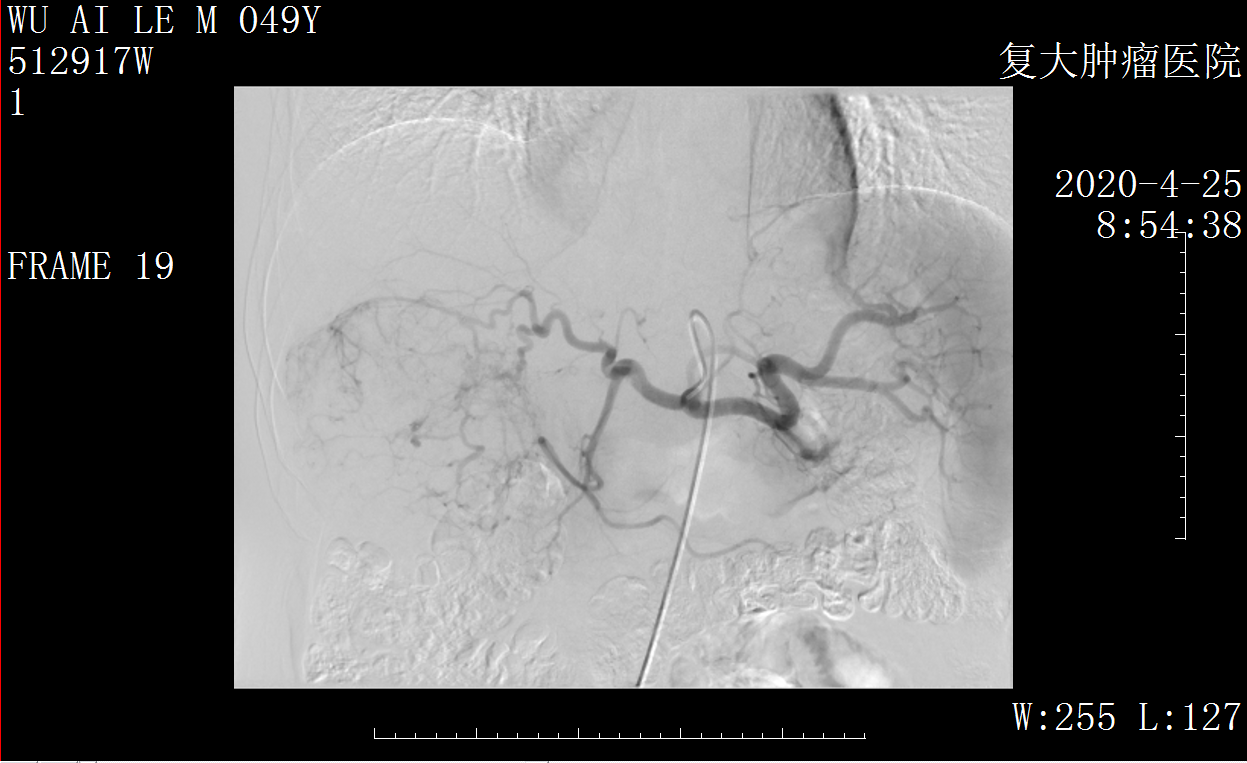

Снимок аппарата DSA в операции